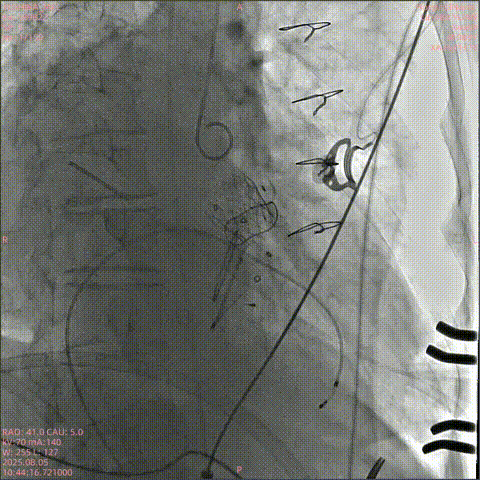

DSA下钢针穿刺心尖,建立心尖入路

输送系统沿加硬导丝进入

瓣膜初次释放,位置稍浅

目标深度:瓣环平mark点

部分回收后,调整瓣膜深度重新释放,瓣膜位置良好

无张力脱钩,瓣膜位置稳定

闭合输送系统后撤除体位,

收紧心尖荷包